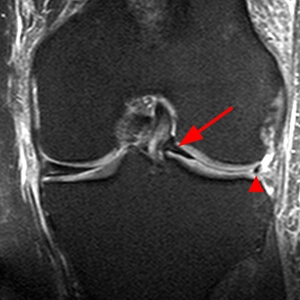

Studiile clinice, experimentale si biomecanice au demonstrat ca meniscurile sunt componente integrante, vitale ale genunchiului. De integritatea lor depinde viitorul genunchiului. De aceea, echipa noastra medicala abordeaza fiecare caz in parte cu ideea de a salva cat mai mult din meniscul afectat. Este foarte important sa intelegem ca nu toate leziunile de menisc au indicatie chirurgicala, dar in acelasi timp, anumite leziuni impun o abordare de urgenta, cu efectuarea cat mai rapida a unei interventii chirurgicale.

Leziunile meniscale sunt de mai multe tipuri:

- Longitudinale

- In toarta de cos

- In toarta de cos deplasate

- Detasari osoase de corn posterior

- Orizontale

- Radiale

- Degenetarive

- In cioc de papagal